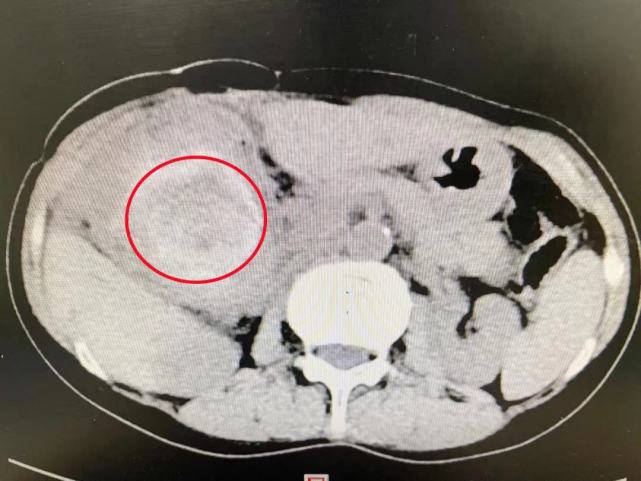

术后大概过了三四年,赵女士又开始出现右上腹痛、寒战、发热的情况。每次发作就吃点药、打点针,不敢也不愿再做第三次手术。直到2021年7月初,上述症状再次发作且比之前更为严重,当地医院CT检查提示“胆总管内巨大结石、肝内多发结石”。从当地医生处了解到湖南省人民医院在肝胆管结石的诊断和胆石病钬激光碎石治疗上有独到之处后,赵女士来到湖南省人民医院汪新天主任医师处就诊,随即被收入胆道外二科病房。

在充分了解患者的病情和诉求后,首席专家吴金术教授带领胆道外二科团队开展术前讨论,根据术前影像判断,结石位于胆总管内,胆总管出现囊状扩张;患者有数十年的胆道梗阻、感染病史,加之做过2次开腹手术,腹腔内粘连的情况肯定很严重,解剖结构难以辨别,手术难度极大。

术中发现,囊肿与门静脉、肝固有动脉、十二指肠、肝脏、胰腺、胃、结肠致密粘连、融合。专家团队凭借高超技艺谨慎操作,仅用3个多小时便从炎性包块中完整取出一个巨大结石,出血量仅50ml。术后测量显示:结石为12×8×7cm3大小、重234g。资料显示,为迄今为止世界上最大的单颗胆总管结石。

“这个手术可以说将失血降至最低,用时最短,对患者打击最小,恢复最快”,术后,胆道外二科护士长胡霞红带领护理团队运用快速康复外科ERAS理念,采用术后多模式镇痛,早期鼓励患者开展机体功能锻炼等措施。术后第二天,患者即可进流食、下床活动;术后第三天复查CT显示:肝内胆管结石已全部取尽,于7月26日康复出院。